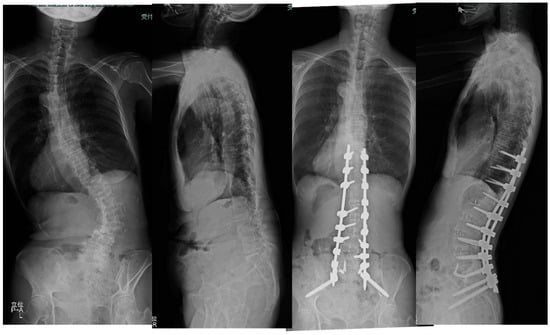

3.1.1. Case 1: 78 Years Old, Female, Degenerative Lumbar Scoliosis

3.1.2. Case 2: 68 Years Old, Female, Adult Scoliosis